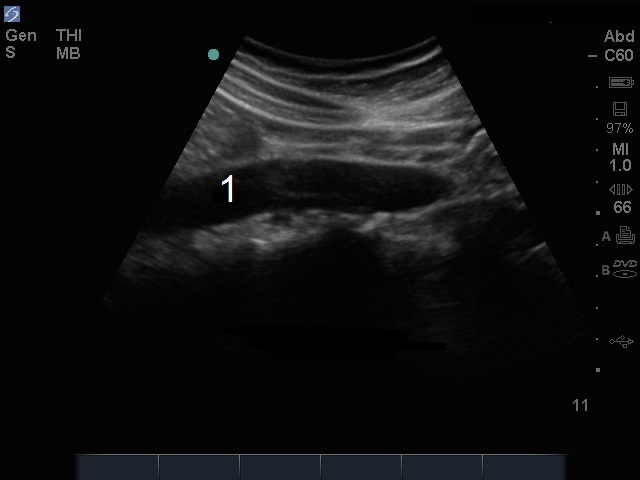

Bild: M-Turbo, distale Aorta, sagittal

M-Turbo: distale Aorta, longitudinale Ansicht

Aorta